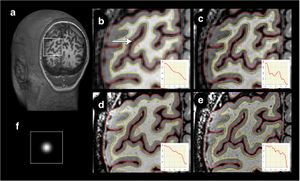

- 1.51 Detailed T1-Weighted Profiles from the Human Cortex Measured in Vivo at 3 Tesla MRI

T1 and T2 relaxometry and mapping of B. braunii colonies. Relaxation measurement was performed using RAREVTR sequence (TR-array, 5500–200 ms; TE, 27–4.5 ms; number of averages, 16; matrix size, 128 x 128; FOV, 0.5 x 0.5mm; resolution was 39 x 39 x 250 μm3). (A) A representative image showing regions of interest (ROI) placed on two representative colonies (one large and one extra-large size colony) for calculating T1 and T2 relaxation times. Scale bar: 500 μm. (B) T1 Map derived from RAREVTR sequence, showing the region of high (white arrow) and low T1 (white arrowhead). Colour scale was generated with Paravision ‘colour 256’ scheme which ranges from 0 to 2500ms. (C) T2 Map Derived from RAREVTR sequence showing a sharp edge of low T2 surrounding all colonies (black arrow). Colour scale ranges from 0 to 40ms. |